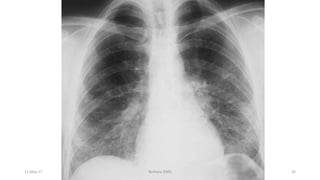

• Chest x ray(RLL,RML lobar pneumonia)

A Pulmonary diseases In HIV

Pulmonary disease is one of the most frequent

complications of HIV infection.

 The most common manifestation of pulmonary

disease is pneumonia.

3 of the 10 most common AIDS-defining illnesses are

recurrent bacterial pneumonia, Tbc and pneumonia

due to the unicellular fungus P. jiroveci.

Other causes of pulmonary infiltrates include other

mycobacteria, other fungi , nonspecific interstitial

pneumonitis, KS, and lymphoma.